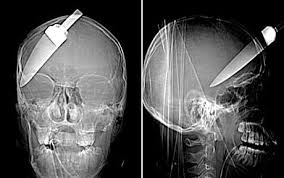

Όλη την τύχη με το μέρος του είχε ένας 13χρονος Κινέζος, ο οποίος κάρφωσε κατά λάθος ένα μαχαίρι στο πρόσωπό του

Το αγόρι προσπαθούσε να καθαρίσει ένα μήλο, αλλά το μαχαίρι του ξέφυγε και καρφώθηκε ακριβώς κάτω από το...

αριστερό μάτι. Η ακτινογραφία που του έβγαλαν οι γιατροί αποκάλυψε ότι η λάμα του μαχαιριού είχε εισχωρήσει πολλά εκατοστά μέσα στο κρανίο του παιδιού, αλλά από θαύμα δεν είχε τραυματίσει τον εγκέφαλό του.

Ο μικρός υποβλήθηκε αμέσως σε επέμβαση για την αφαίρεση του μαχαιριού και αναμένεται να γίνει εντελώς καλά.